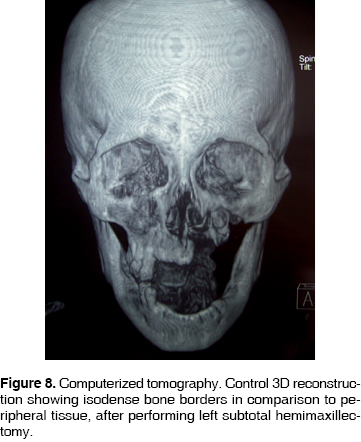

46 year old male with history of uncontrolled type II diabetes mellitus and uncontrolled, 15 year evolution. Systemic arterial hypertension. The patient's condition initiated 3 months prior to the visit; he informed of pain in the upper tooth, which he proceeded to extract himself. Two weeks after this event he experienced painful symptoms in the upper anterior region, informing of halitosis and foul taste in the mouth. He evolved for three months with peri-orbital edema, palpebral occlusion, skin fistula in the left nostril, 0.5 mm fistula intra-orally in the maxillary vestibule, with no egress of purulent matter. A computerized tomography was performed, where lytic areas were observed in the maxillary ascending process and maxillary process of malar bone, the maxillary sinus was invaded (Figure 7). CBC values were as follows: hemoglobin 11.3 g/dL, leukocytes 8.92 cpm, glucose 123 g/dL. Pharmacological treatment was undertaken with clindamycin 600 mg IV every 6 hours and Ceftriaxone, 1 g IV every 12 hours. At a later point, a subtotal hemimaxillectomy was performed preserving the lower orbital ridge. Surgery was performed under balanced inhalation general anesthesia, observing a 5 cm circum-vestibular approach, dissecting tissue until reaching bone exposition. Bone necrotic areas were observed. A 4.5 x 4 cm surgical specimen was harvested. Lesion free bone borders were clinically observed. Sutures were performed with treble cero polyglycolic acid material. The surgical sample was sent to the oral pathologist, who informed of maxillary chronic osteomyelitis with lesion free borders. The patient continued with the following out-patient pharmacological treatment: Procain G Penicillin, 800,000 IU every 12 hours for 30 days. Currently, after 8 months, the patient shows no relapse (Figure 8).